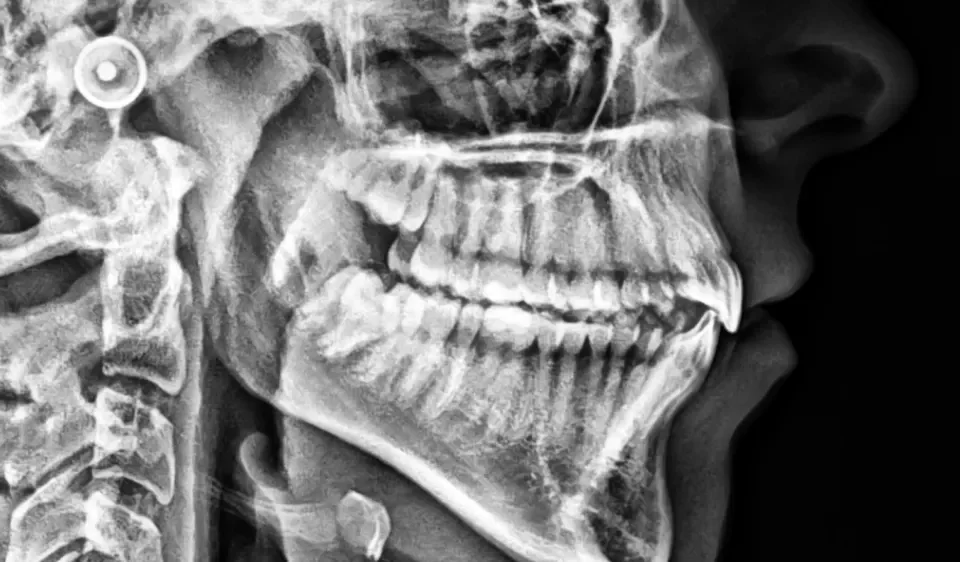

- RTG cefalometryczne, nazywane potocznie „cefalo” lub „tele”, doskonale obrazuje tkanki miękkie twarzy, zatoki przynosowe i podniebienie twarde. RTG cefalometryczne wykonuje się przede wszystkim w diagnostyce wad zgryzu oraz przed planowanym leczeniem ortodontycznym. Cefalo w ortodoncji służy przede wszystkim do oceny wzrostu kostnego i dokonania odpowiednich pomiarów przed kolejnym etapem leczenia.

RTG panoramiczne, RTG cefalometryczne, RTG zatok, a także RTG 1 punktu (3 zębów) lub 2 punktów (6 zębów).